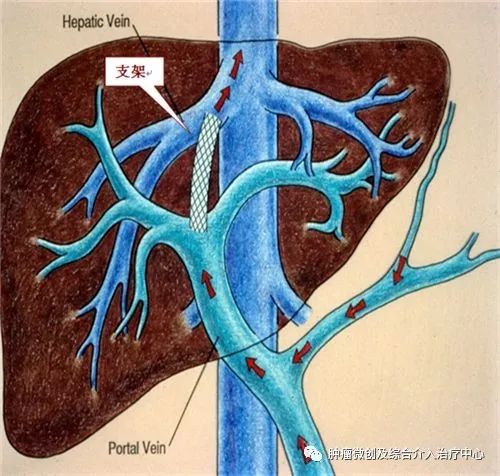

经颈静脉肝内门腔静脉内支架分流术(经颈静脉途径肝内支架门体分流术)TIPS 是治疗门脉高压、上消化道出血的微创介入放射学新疗法。它利用外科分流原理,通过一系列介入器具的使用,在肝实质内肝静脉与门静脉间建立起人工分流通道,从而降低门脉压力、减少或消除由于门脉高压所致的食道静脉曲张破裂出血、腹水等症状。

介入治疗前示意图:

介入治疗后示意图: